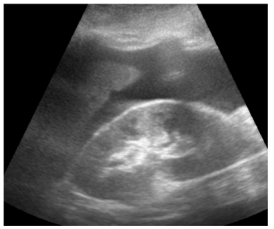

Um paciente de 76 anos de idade deu entrada na UPA, já fora de janela para trombólise, e foi posteriormente encaminhado para a UTI. A imagem apresentada refere-se à tomografia de admissão na UTI.